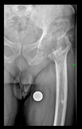

The radiological examination allowed us to verify the close bone-to-implant contact and the unchanged position of the implant during follow-up.

In all the cases operated with the above-described targeting procedure, the stems of the cups remained between the cortical bone surfaces without perforation of the linea terminalis, as shown by postoperative radiographs. There were no complicated surgical situations. In 16 cases, the wound healings were uneventful, and the hips were able to bear weight again after postoperative rehabilitation.